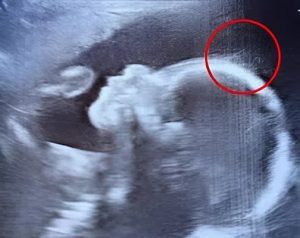

« Un instant… est-ce que ce sont… des cheveux ? », s’exclame-t-il, entre surprise et amusement. Intrigué, un médecin rejoint l’observation et lance, taquin, que le bébé pourrait bien être une future rock star. Sur l’image, de fins filaments semblent danser avec grâce, évoquant des herbes marines bercées par le courant. Un spectacle à la fois fascinant et totalement imprévu.

L’équipe médicale explique alors à Émilie qu’il est tout à fait normal que la pousse des cheveux débute in utero. Ce qui est bien plus rare, en revanche, c’est de pouvoir les distinguer aussi clairement lors de l’examen. Leur longueur et leur densité, visibles à l’écran, dépassent de loin ce que l’on observe habituellement.